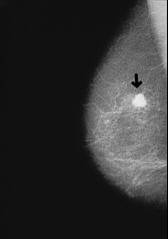

Blood group AB has - like blood group A - a chronic problem of mucus which provokes always a vulnerability for infection diseases: sinusitis, bronchitis, and pneumonia etc.

Example here is an x-ray photo with a pneumonia in the upper half of the right part of the lung.

-- pneumonia, x-ray photo: http://www.doktor.ch/krankheiten/lungenentzuendung.html